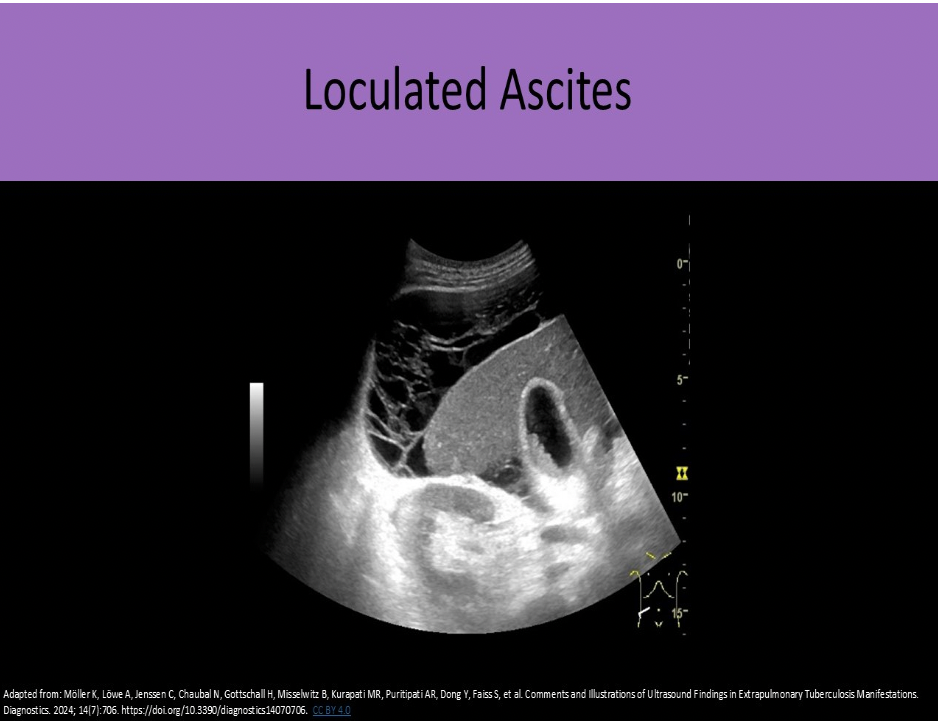

Loculated fluid in the abdomen usually ______, while free fluid in the abdomen will ______

B. displaces adjacent structures, fills spaces around structures

Free fluid in the abdomen tends to fill spaces around the organs, while loculated fluid tends to displace surrounding structures.

Loculated ascites with echogenic debris and matted bowel loops are most suggestive of:

C. peritoneal metastasis

CHF and portal HTN are associated with transudative ascites. The fluid has no cellular debris or proteins and appears anechoic. Free floating bowel loops are a common finding.

Exudative ascites is associated with infection and malignancy. The fluid has echogenic cellular debris and proteins. Loculations and matted bowel loops are common findings.